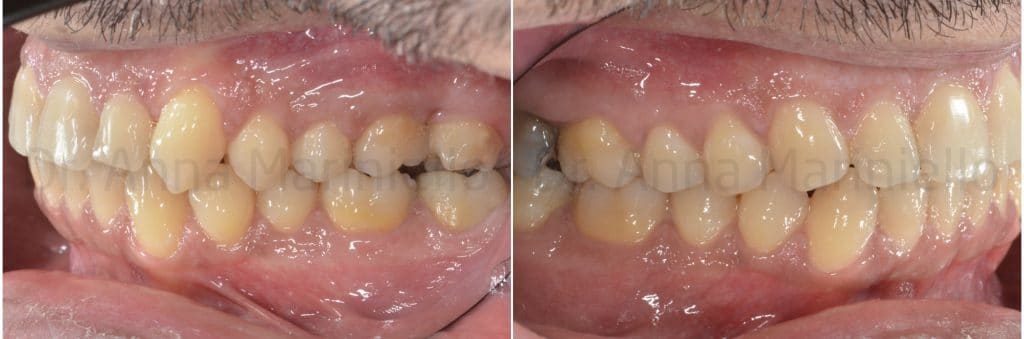

The following photos show the space closure achieved at the beginning of the fourth month:

When we chose to stop 28 mesialization and to use the remaining space only for the distalization from 24 to 26 it has been inserted a palatal miniscrews, mesial to 28.

This miniscrew was used both as distalization anchorage and to stop 28. A .016 – .016 inches stainless steel sectional has been shaped to anchor 28 to miniscrew. Another wire .016 – .016 inches steel has been shaped to realize a sectional bonded from 24 to 26 with an apical loop between 25 and 26. The distalization force was developed by an elastic chain linked on one side to the loop and on the other inserted in the screw’s head.

At the next check we inserted a second miniscrew, mesial and buccal to 28, to apply also buccally the distal force and control a possible rotation of the sector.